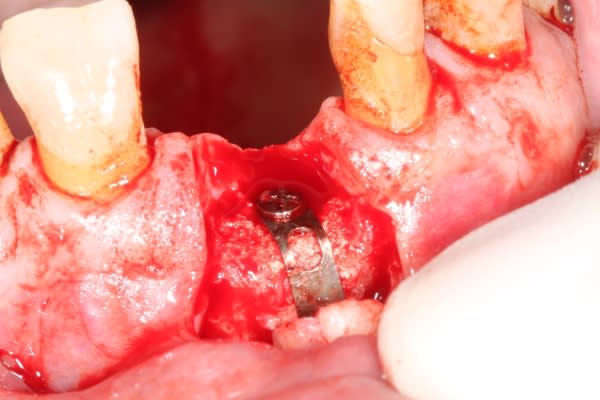

Extraction implantation immédiate mais il y a au moins 7 spires à nue... (photo 1, 2)

dans cette technique un pilier de 2mm de haut est vissé sur l'implant, ce pilier contient un orifice qui permet de transfixer la barre (photo 3,4)

l'espace créé est rempli avec un biomat et le tout est recouvert d'une membrane